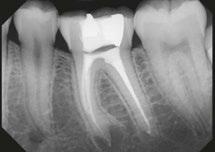

Radiograph of a 30-year-old male who presented with pulp necrosis and symptomatic apical periodontitis. The canals were very long and dilacerated. Dr. Wiseman performed minimal instrumentation in this case due to the dilacerated and calcified canals. The GentleWave procedure was completed. Radiographs viewed are the preoperative 2D and 3D images and the postoperative image. The final radiograph reveals sealer flowing into the isthmus between MB1 and MB2

Radiographs of a 15-year-old male who presented with previous treatment and asymptomatic apical periodontitis. When Dr. Wiseman removed all the gutta percha, the mesial canals were blocked. The GentleWave procedure was completed. The final radiograph reveals sealer that was able to flow into the apical 1/3 of the mesial roots. Radiographs viewed are the preoperative 2D and 3D images and the postoperative image